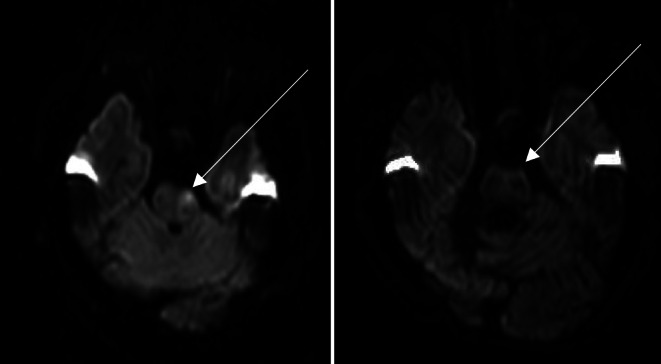

目的:弥散加权成像(DWI)表征急性缺血性脑卒中的梗死核心。DWI可逆性是一种影响脑白质小区域的前循环的现象。本研究旨在明确基底动脉闭塞(BAO)再通成功后后循环DWI可逆性及其对患者预后的影响。方法:回顾性分析2015年1月至2022年12月对脑卒中患者进行分析的两个三级脑卒中中心。纳入标准为急性脑卒中治疗前后MRI及BAO再通成功。脑区被定义为脑干、小脑和幕上脑由后循环供应的脑区。在单因素分析中对这些区域进行比较。其次,比较DWI可逆性患者和无DWI可逆性患者的预后,单因素分析以预后良好为主要终点(mRS 90d 0 ~ 2)。结果:总共有5/28的纳入患者(21.74%)显示DWI可逆性,DWI可逆性仅发生在脑干。与小脑或幕上梗死相比,脑干梗死的总体范围与患者预后的相关性更好(Spearman ρ = 0.757;p 结论:急性脑卒中合并BAO患者脑干DWI限制可逆性明显。在这项研究中,与小脑或幕上梗死相比,患者预后与脑干梗死的范围相关性更强。

Results: In total, 5/28 of included patients (21.74%) showed DWI reversibility, which was exclusively found in the brainstem. The overall extent of brainstem infarction correlated better with patient outcome compared to cerebellar or supratentorial infarction (Spearman's ρ = 0.757; p < 0.001). Good outcome was more frequent in patients with DWI reversibility compared to those without (mRS 0-2, DWI+ n = 4, 80% vs. DWI- n = 6, 26%, p = 0.023).

Conclusion: DWI restriction reversibility was observed in the brainstem of acute stroke patients with BAO. In this study, patient outcome correlates stronger with the extent of brainstem infarction compared to cerebellar or supratentorial infarction.